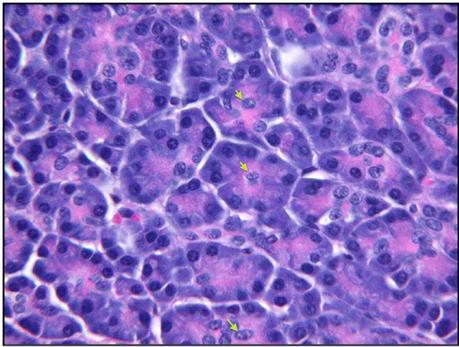

Glandular epithelium: pancreas

(exocrine, acinar)